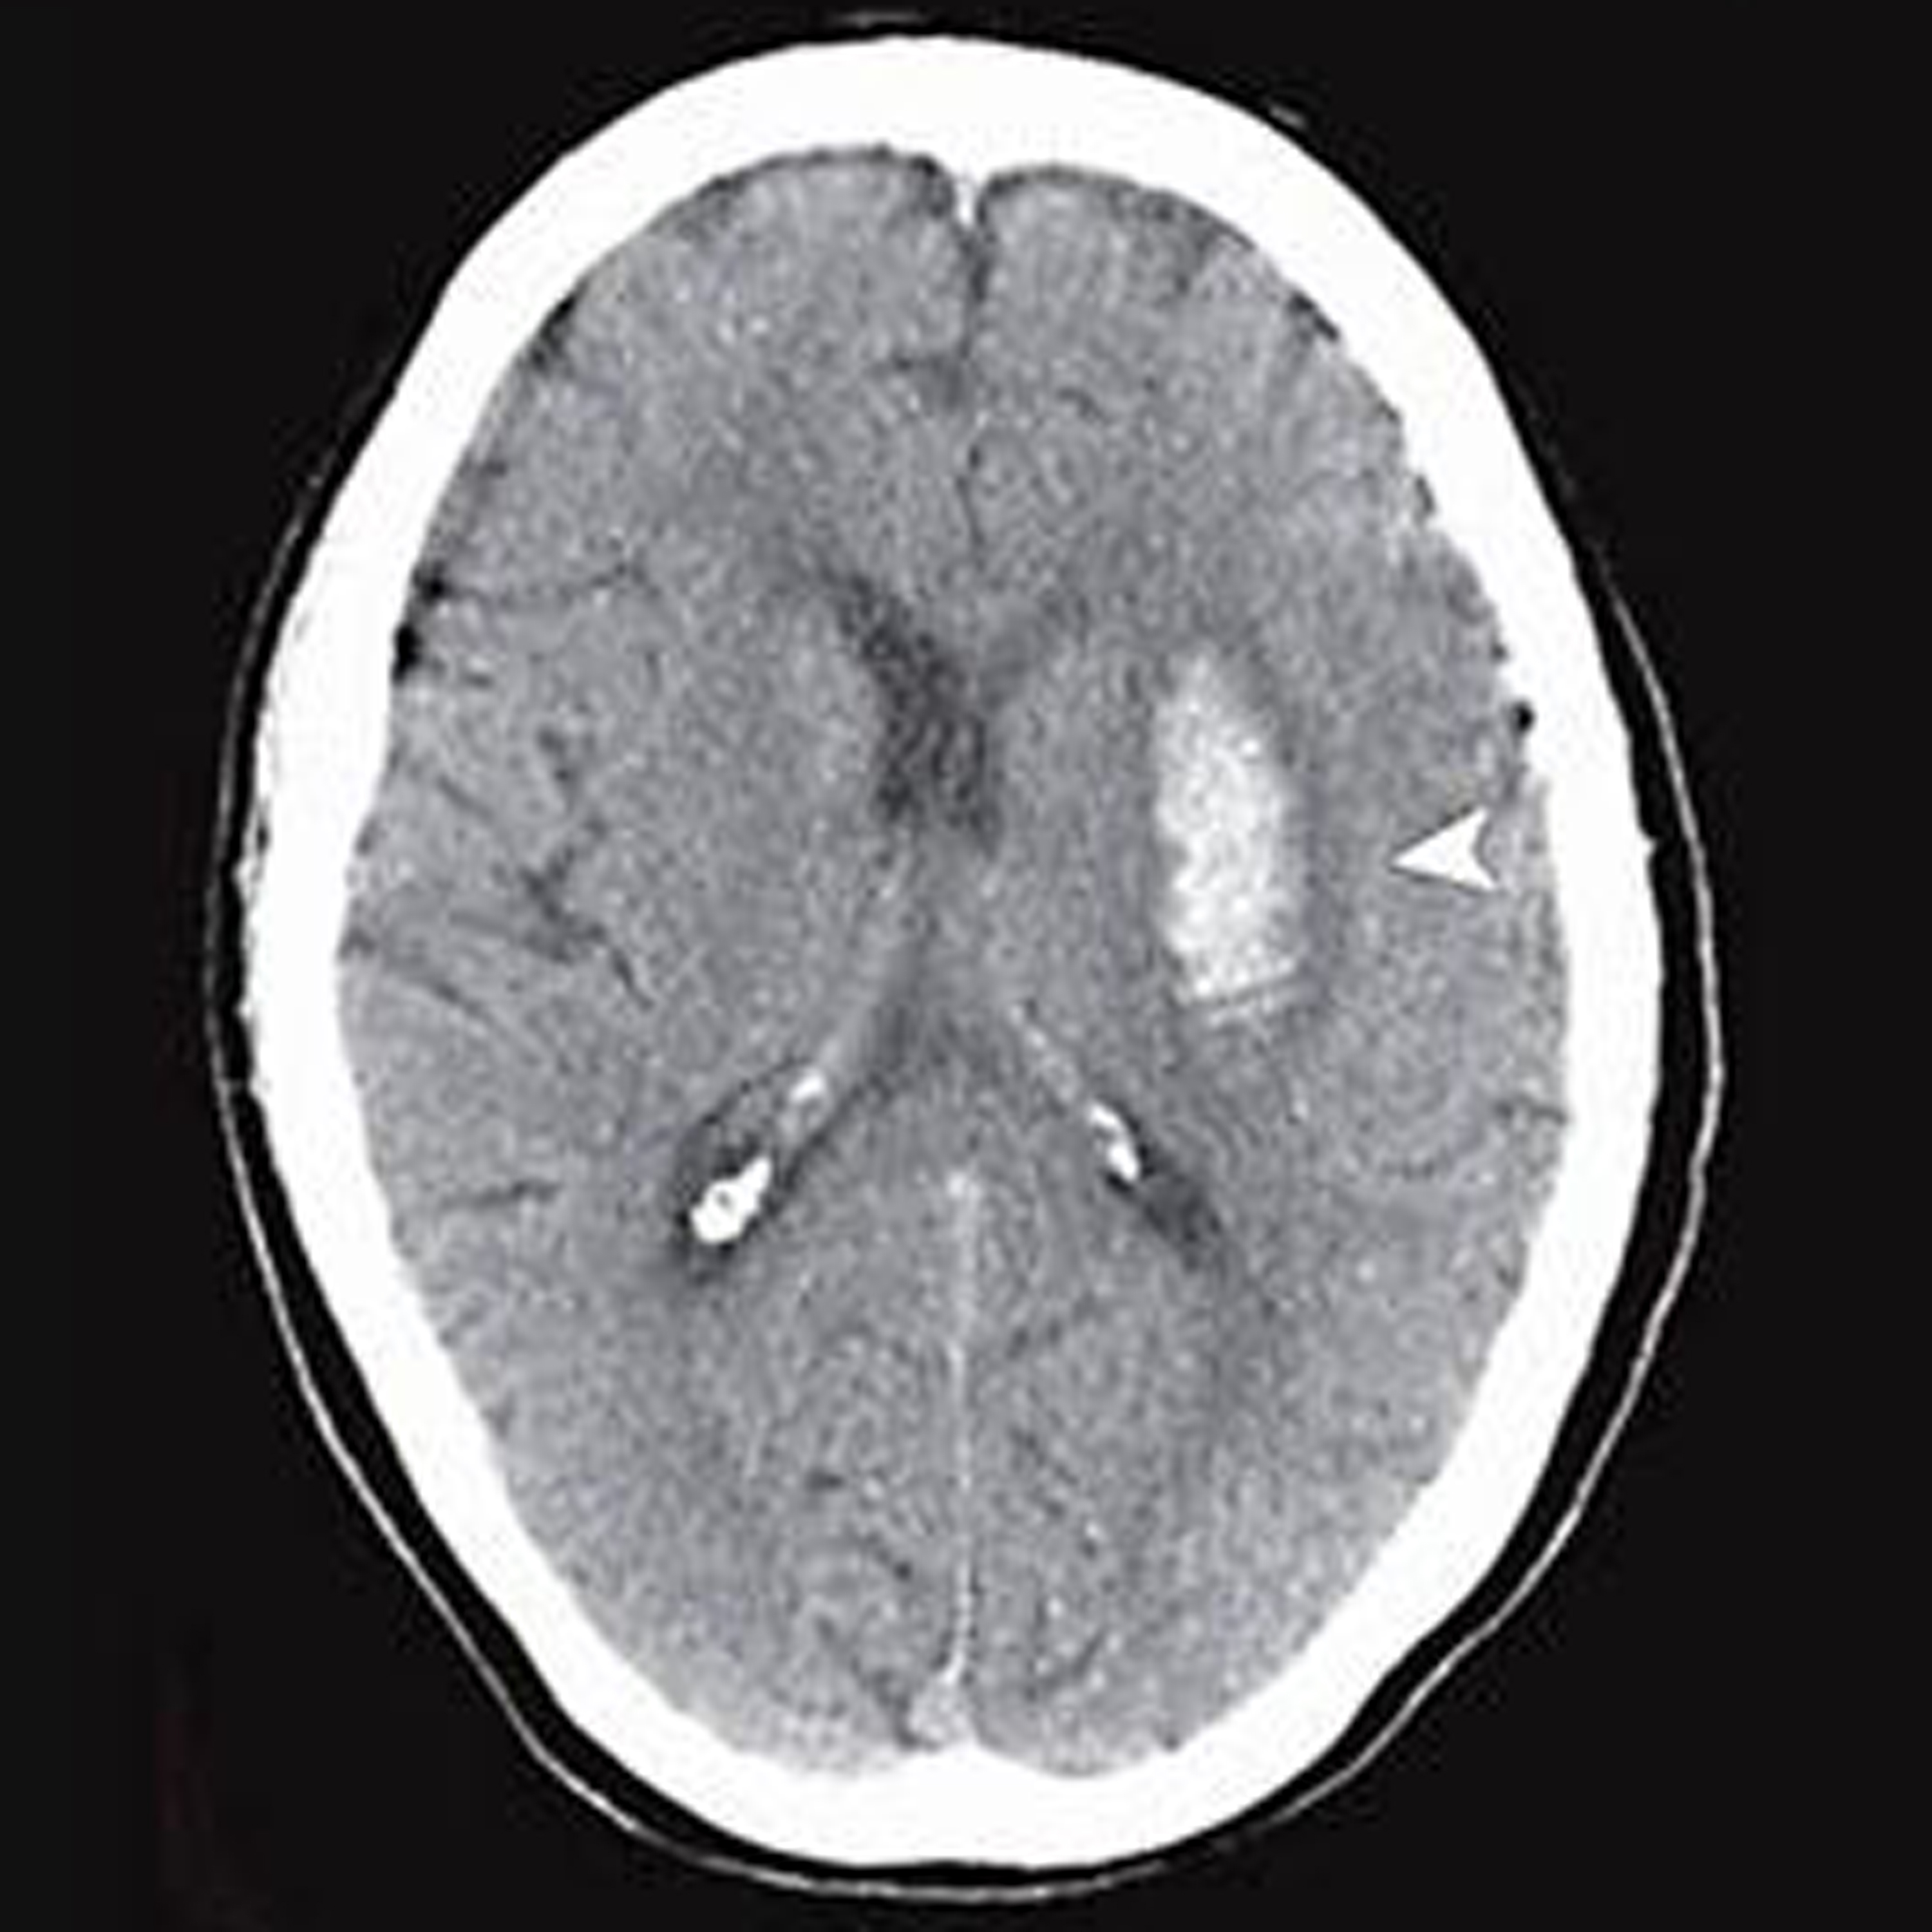

Association of Recent Use of Non–Vitamin K Antagonist Oral Anticoagulants With Intracranial Hemorrhage Among Patients With Acute Ischemic Stroke Treated With Alteplase